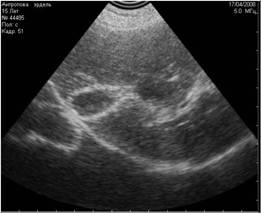

Рис. 11. Истинные тени, испускаемые скелетными структурами плода шелти на 36 день беременности. Первичными очагами минерализации являются череп и таз плода. На этом снимке мы видим две тени, испускаемые этими структурами. |